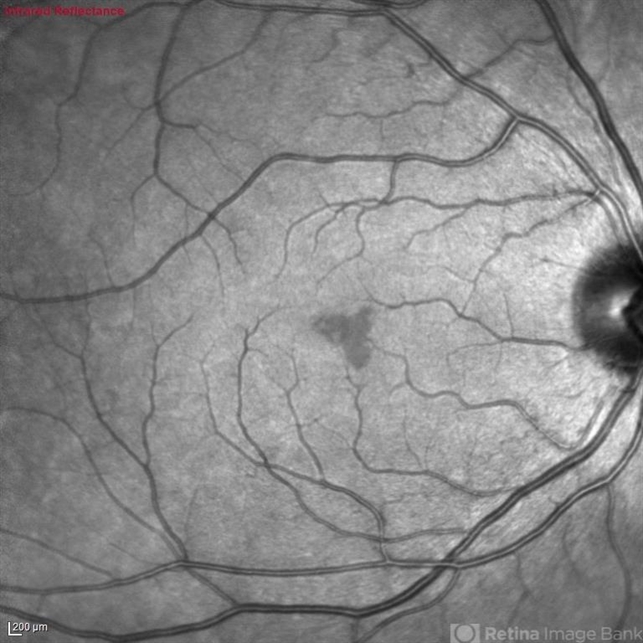

- infrared image

Optical coherence tomography system

Heidelberg Spectralis - Description

- Infrared fundus of a 30 yo female with PAMM OD.